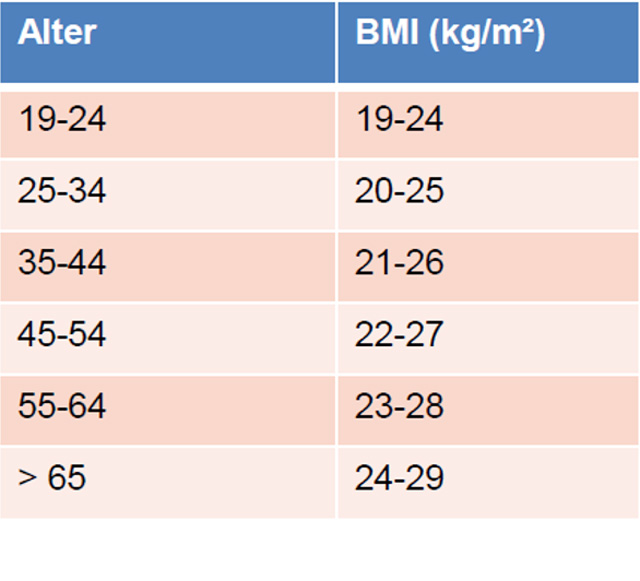

Der Body Mass Index

Zusammen mit der Körpergrösse kann über die Formel Körpergewicht (Kg) /Körpergrösse2 (m2) der so genannte Body Mass Index, der BMI berechnet werden.

Auch dieser Wert unterliegt gewissen Limitationen.

Zwar definiert die WHO über den BMI Übergewicht und Adipositas (Fettleibigkeit), jedoch ist der Wert gerade bei Sportlern schwierig zu bewerten, da der oftmals erhöhte Anteil der Muskelmasse den Wert verfälschen kann.

Body Mass Index Tabelle